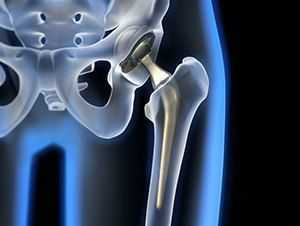

Рентгенография тазобедренного сустава

Тазобедренный сустав является сложным многоосным сочленением, которое выполняет сгибание/разгибание, отведение/приведение, пронацию и супинацию бёдер и принимает на себя серьёзную нагрузку. Любые нарушения в его функционировании не только приводят к серьёзному дискомфорту для человека, но и могут стать причиной развития серьёзных нарушений. Рентген тазобедренного сустава (ТБС) — это неинвазивный диагностический метод, ценность которого сложно переоценить.

Он нашёл широкое применение в разных областях медицины, включая травматологию, ревматологию, ортопедию, гнойную хирургию для диагностики заболеваний и последствий перенесённых травм, для определения объёма предстоящей операции или эффективности проведённого лечения. Процедура достаточно безопасна, высокоэффективна и проста, но при этом позволяет получить ценные данные о состоянии ТБС пациента.

Проведение рентгенографии ТБС

Стандартная рентгенография тазобедренного сустава проводится в 2-х проекциях. Помимо прямой используют вспомогательную, которая может быть боковой или задней косой, предусматривающей отведение бедра. Выбор, в данном случае, зависит от целей исследования и характера нарушений у пациента.

Рентгенография тазобедренного сустава в прямой проекции

Пациент принимает положение лёжа на спине, выпрямив нижние конечности. Стопа со стороны поражения должны быть повёрнута кнутри. Такое положение тела пациента обеспечивает хороший обзор медиальной части шейки бедра и даёт возможность определить медиальные переломы.

Рентгенография ТБС в косой проекции

Пациент принимает положение лёжа на спине, поражённая конечность согнута в колене и повёрнута кнаружи при косой проекции. В случае, если имеется подозрение на перелом бедра, локализующийся в области шейки, косую проекцию не используют, поскольку она может привести к смещению отломков кости и усугубить ситуацию.

Рентгенография ТБС в боковой проекции

Пациент принимает положение лёжа на спине, поражённая конечность согнута в колене и бедре под углом 90°. Под пятку ставят специальную подставку, трубку рентгена располагают сбоку со стороны здоровой ноги.